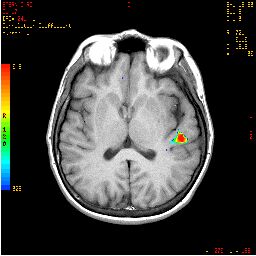

Activación auditiva no verbal

Escuchar música de forma pasiva

Activación

Derecha > Circunvoluciones de Heschl izquierdas